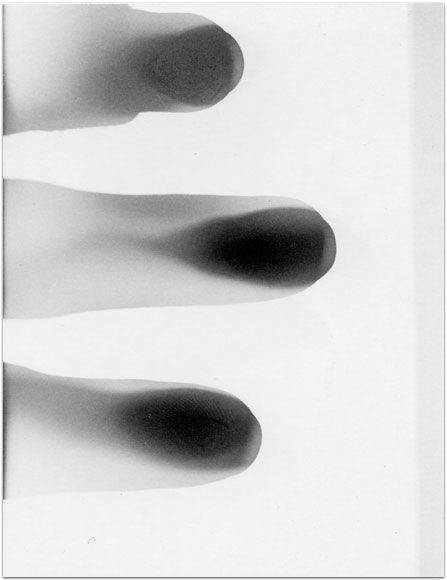

- Itis

- 2004

- 3.25″ × 4.25″

- Photographic montages of my hands & health paraphernalia on Polaroid Type 664 & 669 Film using a Daylab Printer.

- Frustrated by a lack of mobility and severe pain with my fingers, unable to accomplish any task requiring joint dexterity,

I noticed piles of health related papers strewn around. I layered these in a slide printer without removing

my hands, enlarging both onto the film.